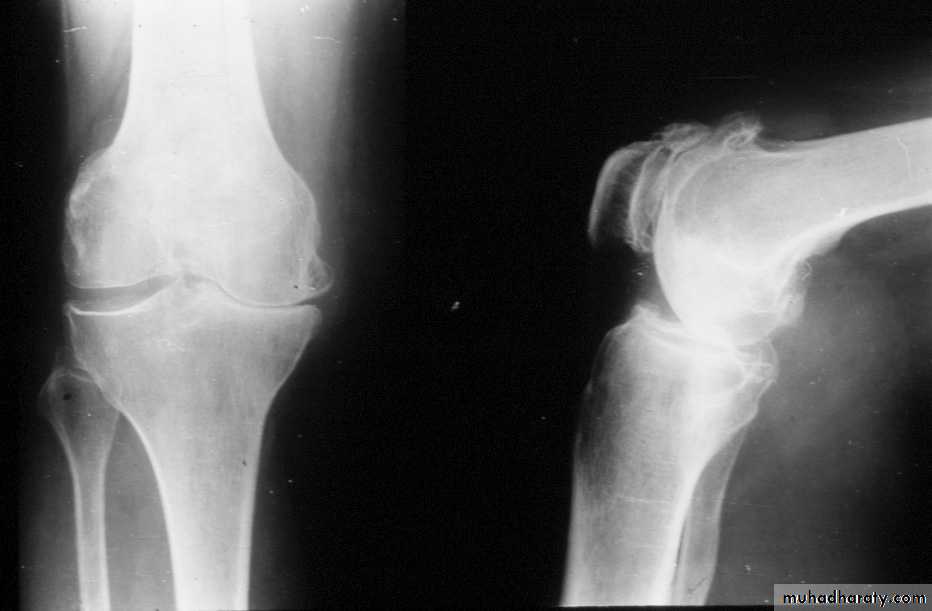

Radiographic features of OA

1- Asymmetric loss of cartilage ( narrowing of joint space).2-Sclerosis of subchondral bone, with subchondral cyst sometimes.

3- Osteophytes (spurring of the joint margins directed toward joint line).